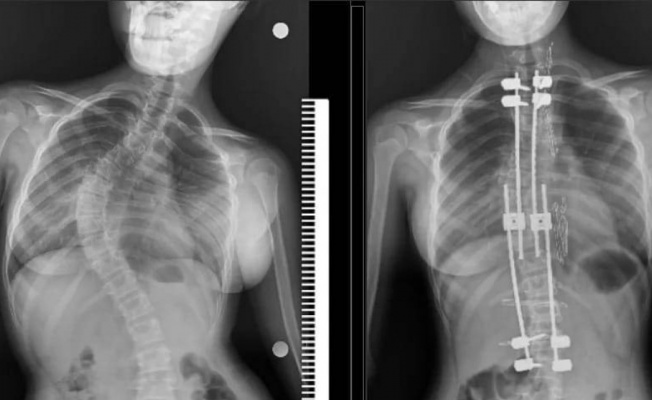

Samsun’un Bafra ilçesinde yaşayan 10 yaşındaki Zümra Demircioğlu bel ve sırt bölgesinde aşırı ağrı ve günlük aktivitelerini yapmakta zorlanma şikayetleri nedenleriyle Samsun Eğitim ve Araştırma Hastanesi’ne başvurdu. Burada çekilen röntgen ve yapılan tetkikler sonucunda 75 derece omurga eğriliği tespit edilen minik Zümra için ameliyat kararı verildi. Büyüme koruyucu sisteminin uygulandığı ameliyatta minik Zümra’nın omurgası düzeltildi. Özel hastanelerde ortalama 300 ile 500 bin TL arasında yapıldığı öğrenilen bu ameliyat artık Samsun Eğitim ve Araştırma Hastanesi’nde ücretsiz olarak gerçekleştiriliyor.

Ameliyat hakkında bilgi veren Dr. Ömer Bozduman, "Bu gibi durumlarda uzayan rot dediğimiz bir sistem uyguluyoruz. Bunun nedeni çocukları yaşı küçük olduğu için füzyon dediğimiz kaynatma ameliyatı yaparsak akciğerlerinde yetersiz gelişme, göğüs kafeslerinde yetersiz gelişme ve kanallarında yetersiz gelişme oluşabileceği için büyüme koruyucu cerrahi yapıyoruz. Büyüme koruyucu cerrahinin diğer füzyon cerrahisinden alternatifi şudur: Düzenli aralıklarla düzeltme yapıyoruz. Çocuk büyüdükçe biz de bu sistem anestezi altında ya da anestezisiz olarak uzatarak çocuğun yeterli omurga büyüklüğüne ulaştıktan sonra yeterli kalıcı ameliyatı gerçekleştiriyoruz. Anestezi hocamız Doç. Dr. Serkan Turgal yardımı ile bu ameliyatı başarıyla gerçekleştirdik. 10 yaşındaki hastamıza büyüme koruyucu sistemi yerleştirdik. Düzenli aralıklarla uzatmalarını yapacağız. Nihai ameliyatını omurgası büyüdükten sonra gerçekleştireceğiz. Eğitim ve Araştırma Hastanesi olarak bir ilki gerçekleştirdik. Hastamız gayet iyidir. Birinci günün kalkıp yürüdü. Dördün gün sonra taburcu ettik. Herhangi bir nörolojik veya başka bir sorunla karşılaşmadık. İhtiyacı olan tüm hastalarımıza Samsun Eğitim ve Araştırma Hastanesi olarak devletimizin imkanlarıyla bu hizmeti ücretsiz olarak veriyoruz. Aileler bu semptomlar hakkında dikkatli olmalıdır. En ufak şüphede polikliniklerimize bekliyoruz. Bizler yardımcı olacağız" diye konuştu.